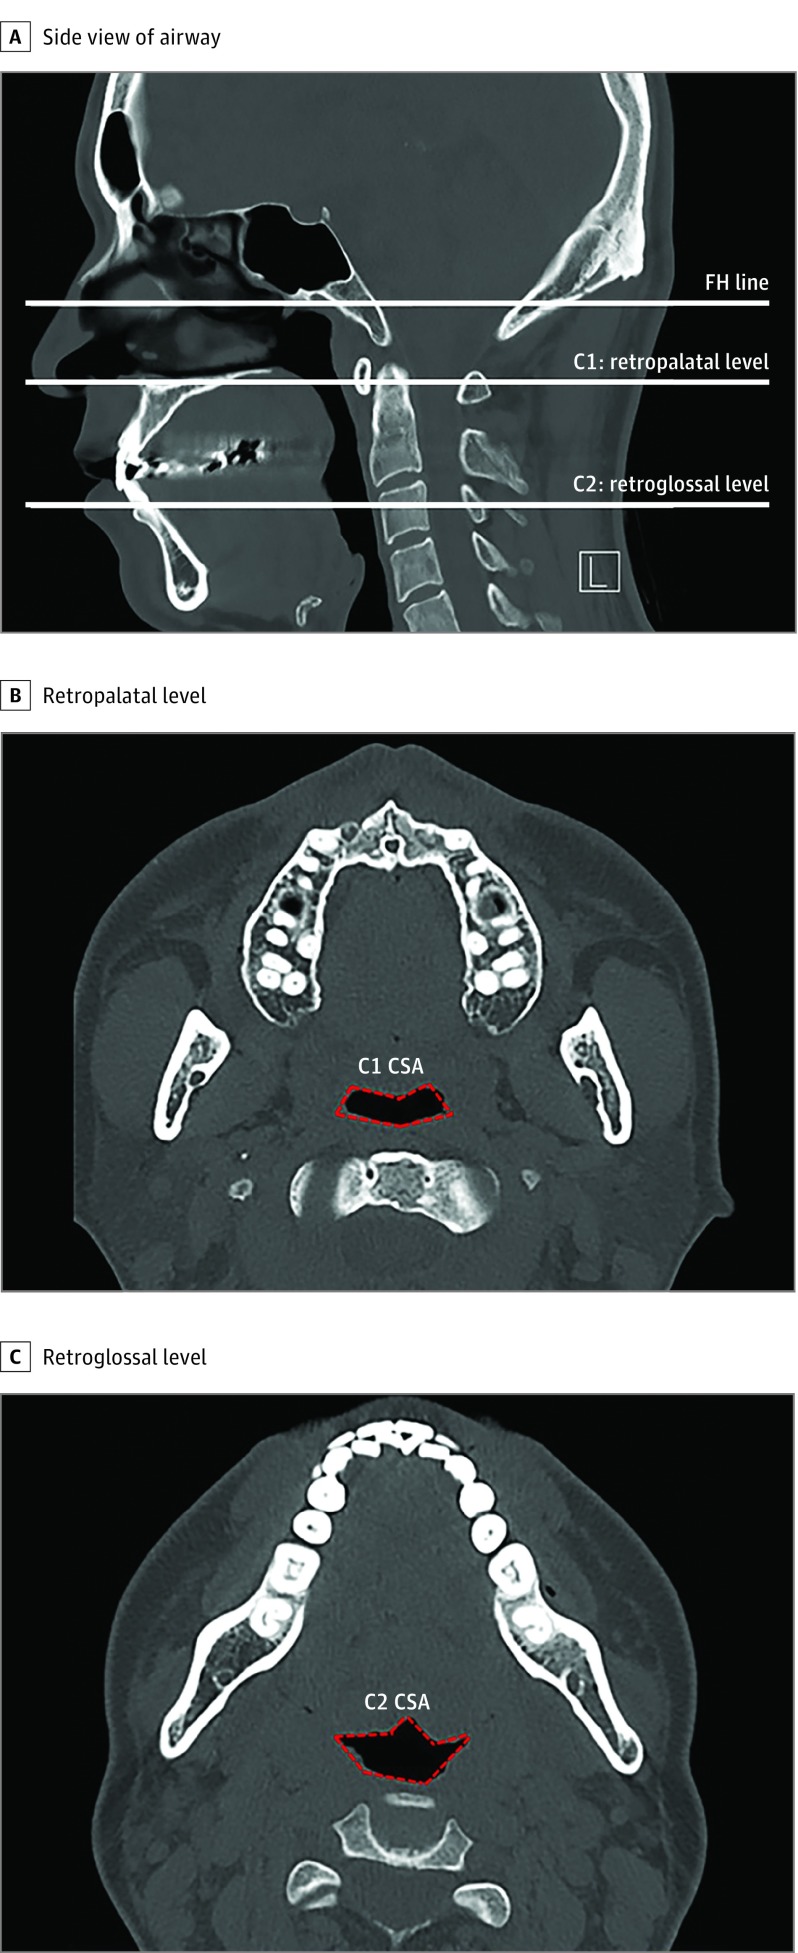

To evaluate changes in the pharyngeal airway at the retropalatal and retroglossal levels, the cross-sectional area (CSA) on each axial plane (C1, C2) was evaluated (Figure 1A). The CSA values of the retropalatal and retroglossal space of 61 of the patients were measured both before and 3 months after the operation by using computed tomographic scans of the paranasal sinuses (Figure 1B and C). To avoid the changes in upper airway lumen during respiration, all participants were asked to hold their breath at the end of expiration for each scan. Changes in the CSA were measured using a method described for the Superimposition module of the Invivo 5 program.22

Figure 1. Measurement of Airway Diameter or Upper Airway Volume Using Computed Tomographic Scan of the Paranasal Sinuses.

A, Sagittal view. The C1 and C2 planes, parallel to the Frankfort horizontal (FH) plane, are tangent to the most caudal medial projections of cervical vertebrae 1 and 2, respectively. B, Axial view. Cross-sectional area (CSA) of the retropharyngeal space (outlined in red). C, Axial view. Cross-sectional area of retroglossal space (outlined in red). L indicates left. All computed tomographic scans were non–contrast enhanced.